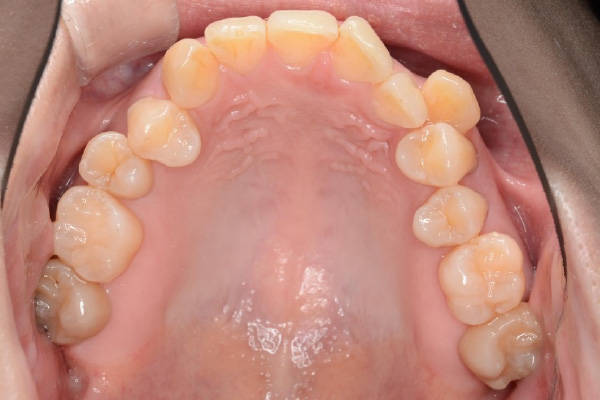

【30代女性】

八重歯と前歯で噛めないのを

インビザライン矯正で

治療したケース

治療前

| 主訴 | 八重歯、前歯で噛めないのが気になる |

|---|---|

| 期間 | 2年半 |

| 費用 | 220,000円〜660,000円 (デンタルローン 3,100〜6,600円/月) |

| 治療内容 | インザライン矯正 非抜歯 |

| 治療に伴うリスク | ・矯正終了後は、リテーナーを指示通りに使用し、歯の後戻りを防ぐ必要があります。 |